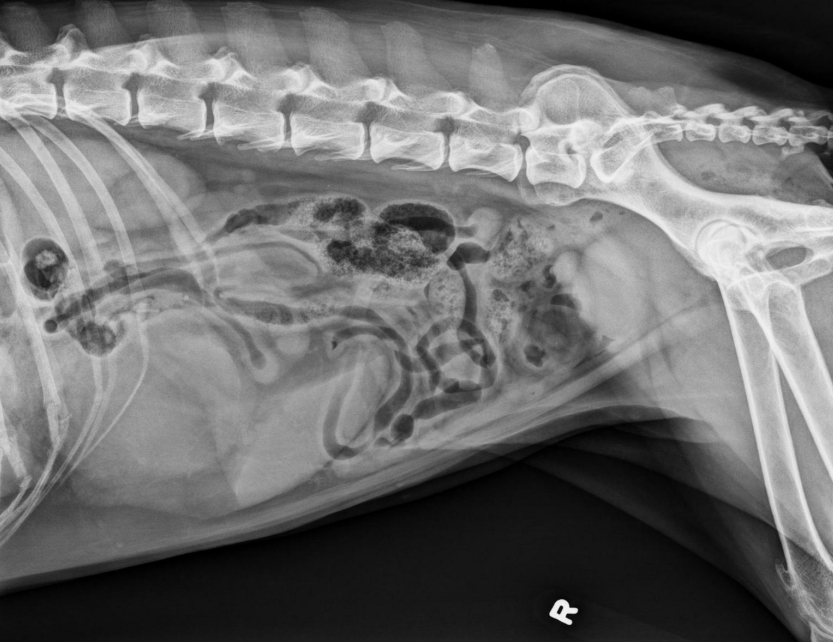

●9 yo mixed breed female dog

(sterilized)

●Increased ALP

● Impressive amount of subcutaneous and intra-abdominal fat.

● Enlarged liver – changed gastric axis pushed caudally, rounded edges, extending past the costal arch.

● At least two round soft tissue opacity structures superimposed on ventral liver (lateral view).

● Round soft tissue structure cranial to right kidney.

● Mass in adrenal gland or pancreas

● Hepatic nodules (benign vs metastatic disease)

SI gas is normal because bowels empty.